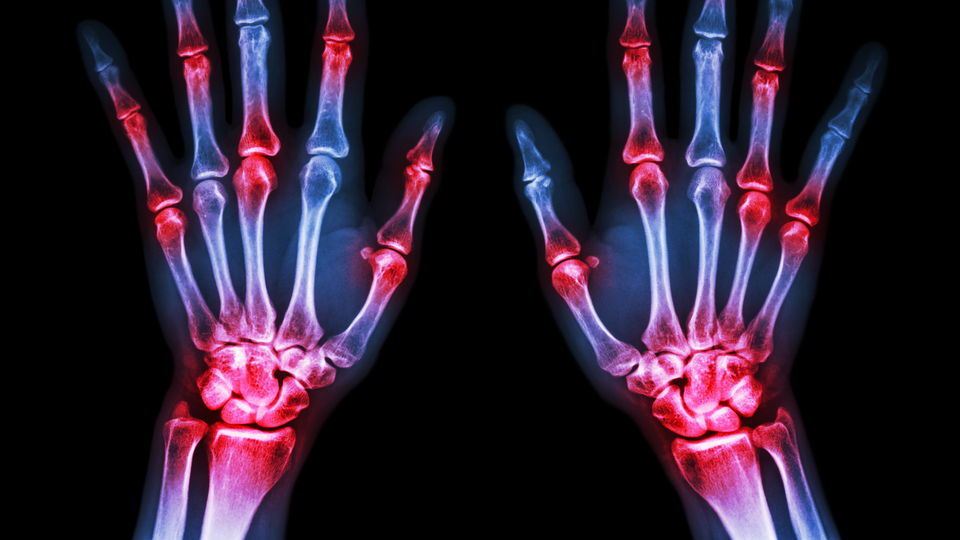

ABD'de Harvard Üniversitene bağlı Brigham Kadın Hastanesinden uzmanlar, çocuklukta ebeveynlerin içtiği sigara dumanına maruz kalınmasıyla ileri yaşta artan seropozitif romatoid artrit (RA) riski arasında doğrudan potansiyel ilişkili olduğunu tespit etti.

ROMATOİD ARTRİT RİSKİ YÜZDE 75 ARTIYOR

Araştırma, çocuklukta ebeveynlerin içtiği sigaranın dumanına maruz kalanlarda RA olasılığının yüzde 75 artırdığı görüldü.

Bulgular, "Arthritis & Rheumatology" dergisinde yayımlandı.

Brigham'ın Romatoloji, Enflamasyon ve Bağışıklık Bölümünden uzman Kazuki Yoşida, "Bulgularımız, en sık rastlanılan otoimmün hastalıklardan biri olan RA ile ilişkili olarak, sigaranın sağlığa olumsuz etkilerine daha fazla derinlik ve önem katıyor" değerlendirmesini yaptı.